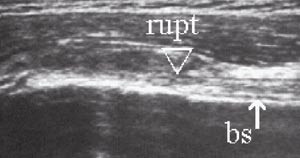

Bicepsseneruptur finnes isolert eller i forbindelse med rotatorcuffruptur. Kriteriene for ruptur er avbrekk av den fibrillære senestrukturen i lengdesnitt (e-fig 13) og manglende senefremstilling i sulcus intertubercularis i tverrsnitt (1, 3).